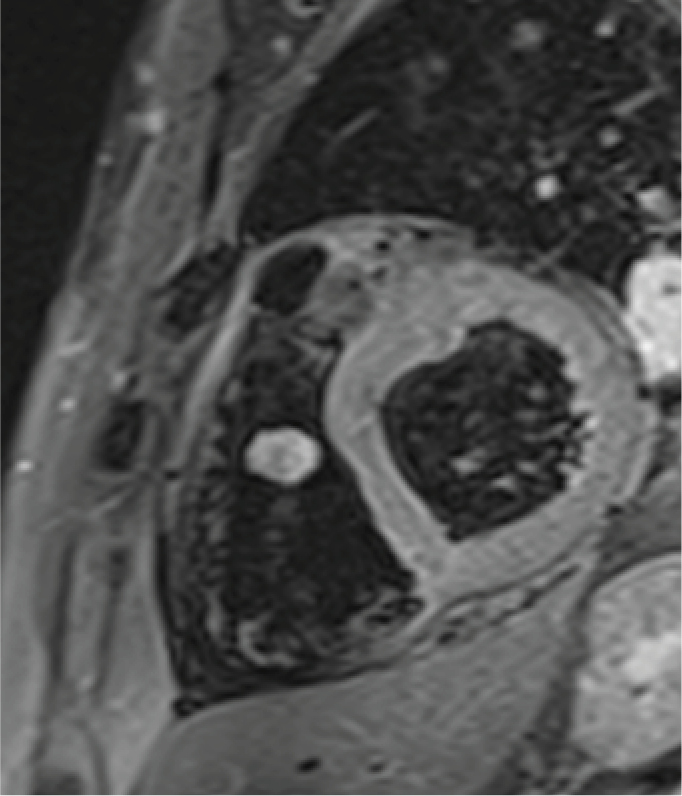

Resonancia magnética cardiaca

La resonancia magnética cardiaca es un una técnica de imagen que permite estudiar detalladamente y en una sola exploración la función y la estructura del corazón. Este auxiliar diagnóstico utiliza un potente campo magnético, sin radiación, para generar imágenes detalladas de las estructuras del corazón.

La resonancia magnética esta indicada en la evaluación de las cardiopatías congénitas tanto en el niño como en el adulto, en la evaluación de la perfusión miocárdica (resonancia cardiaca con gadolinio), de la función cardiaca, de las enfermedades del músculo cardiaco (miocardiopatías), tumores del corazón y del tejido que rodea al corazón (pericardio).

Este estudio es bien tolerado por la mayoría de las personas. El campo magnético no es dañino, pero puede causar el mal funcionamiento de algunos dispositivos médicos. La mayoría de los implantes ortopédicos no presentan riesgos, pero siempre debes informar al técnico de resonancia magnética si tiene algún dispositivo o metal en su cuerpo.